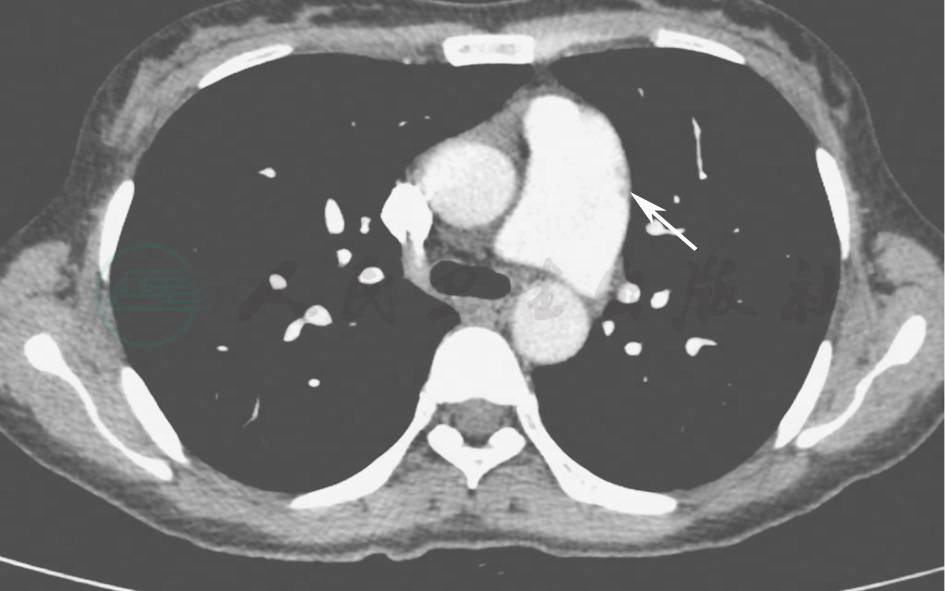

【影像学检查】

胸部CT(2014年10月16日):双肺散在小结节影,未见结节空洞改变、肺门和纵隔淋巴结肿大和胸腔积液征象(图1)。

图1 胸部CT表现(2014-10-16)